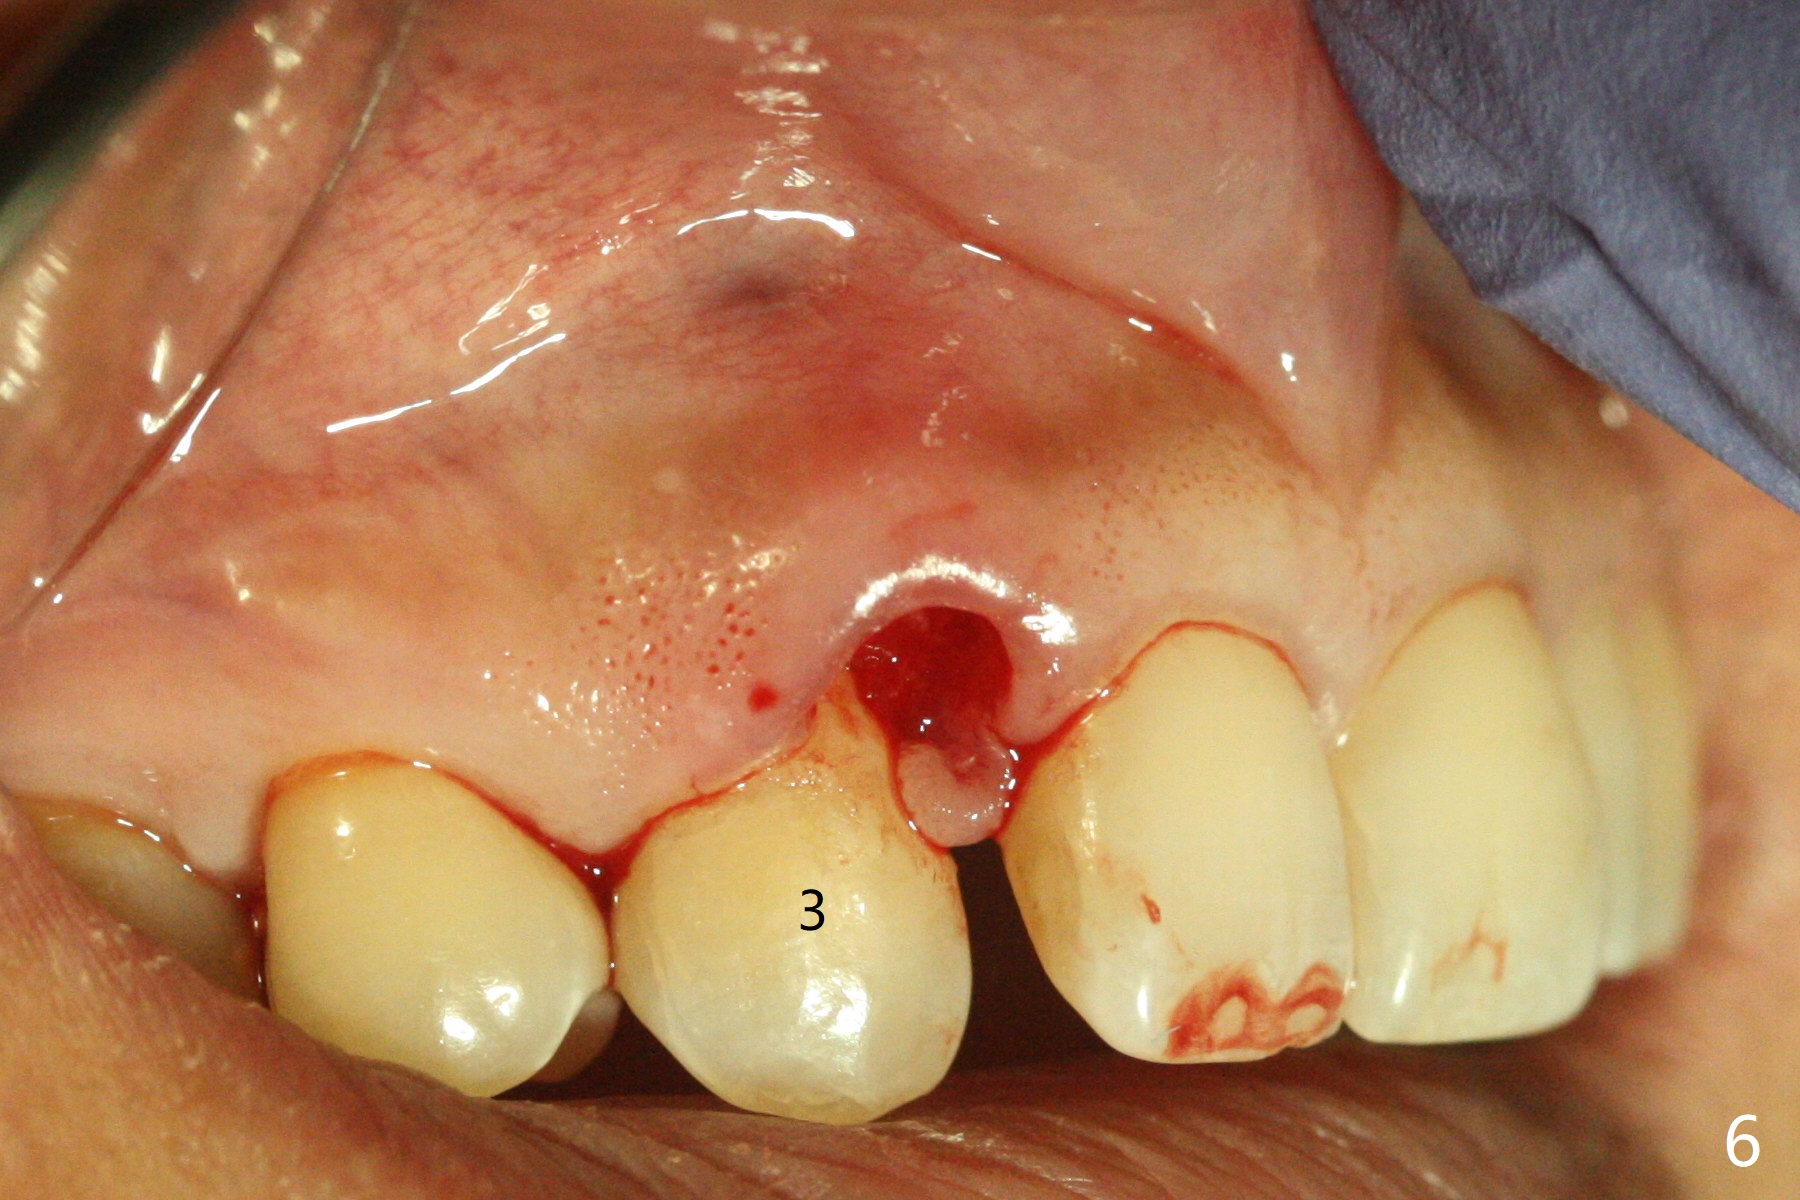

A 54-year-old woman seeks treatment for the tender upper right lateral incisor (Fig.1-4: 2 because of palatal cervical caries (Fig.3 <) and periapical radiolucency (*)), which overlaps with the palatal canine (3). One of treatment options is to extract the lateral and to orthodontically move the canine to the position of the lateral, particularly the root (Fig.5 arrow). When the lateral is removed, the labial bone of the canine is thin (Fig.6). Allograft is placed (Fig.8 * and dashed line), covered with Amnion-Chorion Allograft (Bioxclude) and sutured with 4-0 PGA (Fig.7). The wound heals 9 days postop (Fig.9,10). The patient is grateful because of no pain, which she thinks is due to bone graft, whereas Amnion-Chorion membrane is another contributory factor. The lateral root convexity remains 1 month postop (Fig.11 *); she is undecided upon orthodontic treatment.